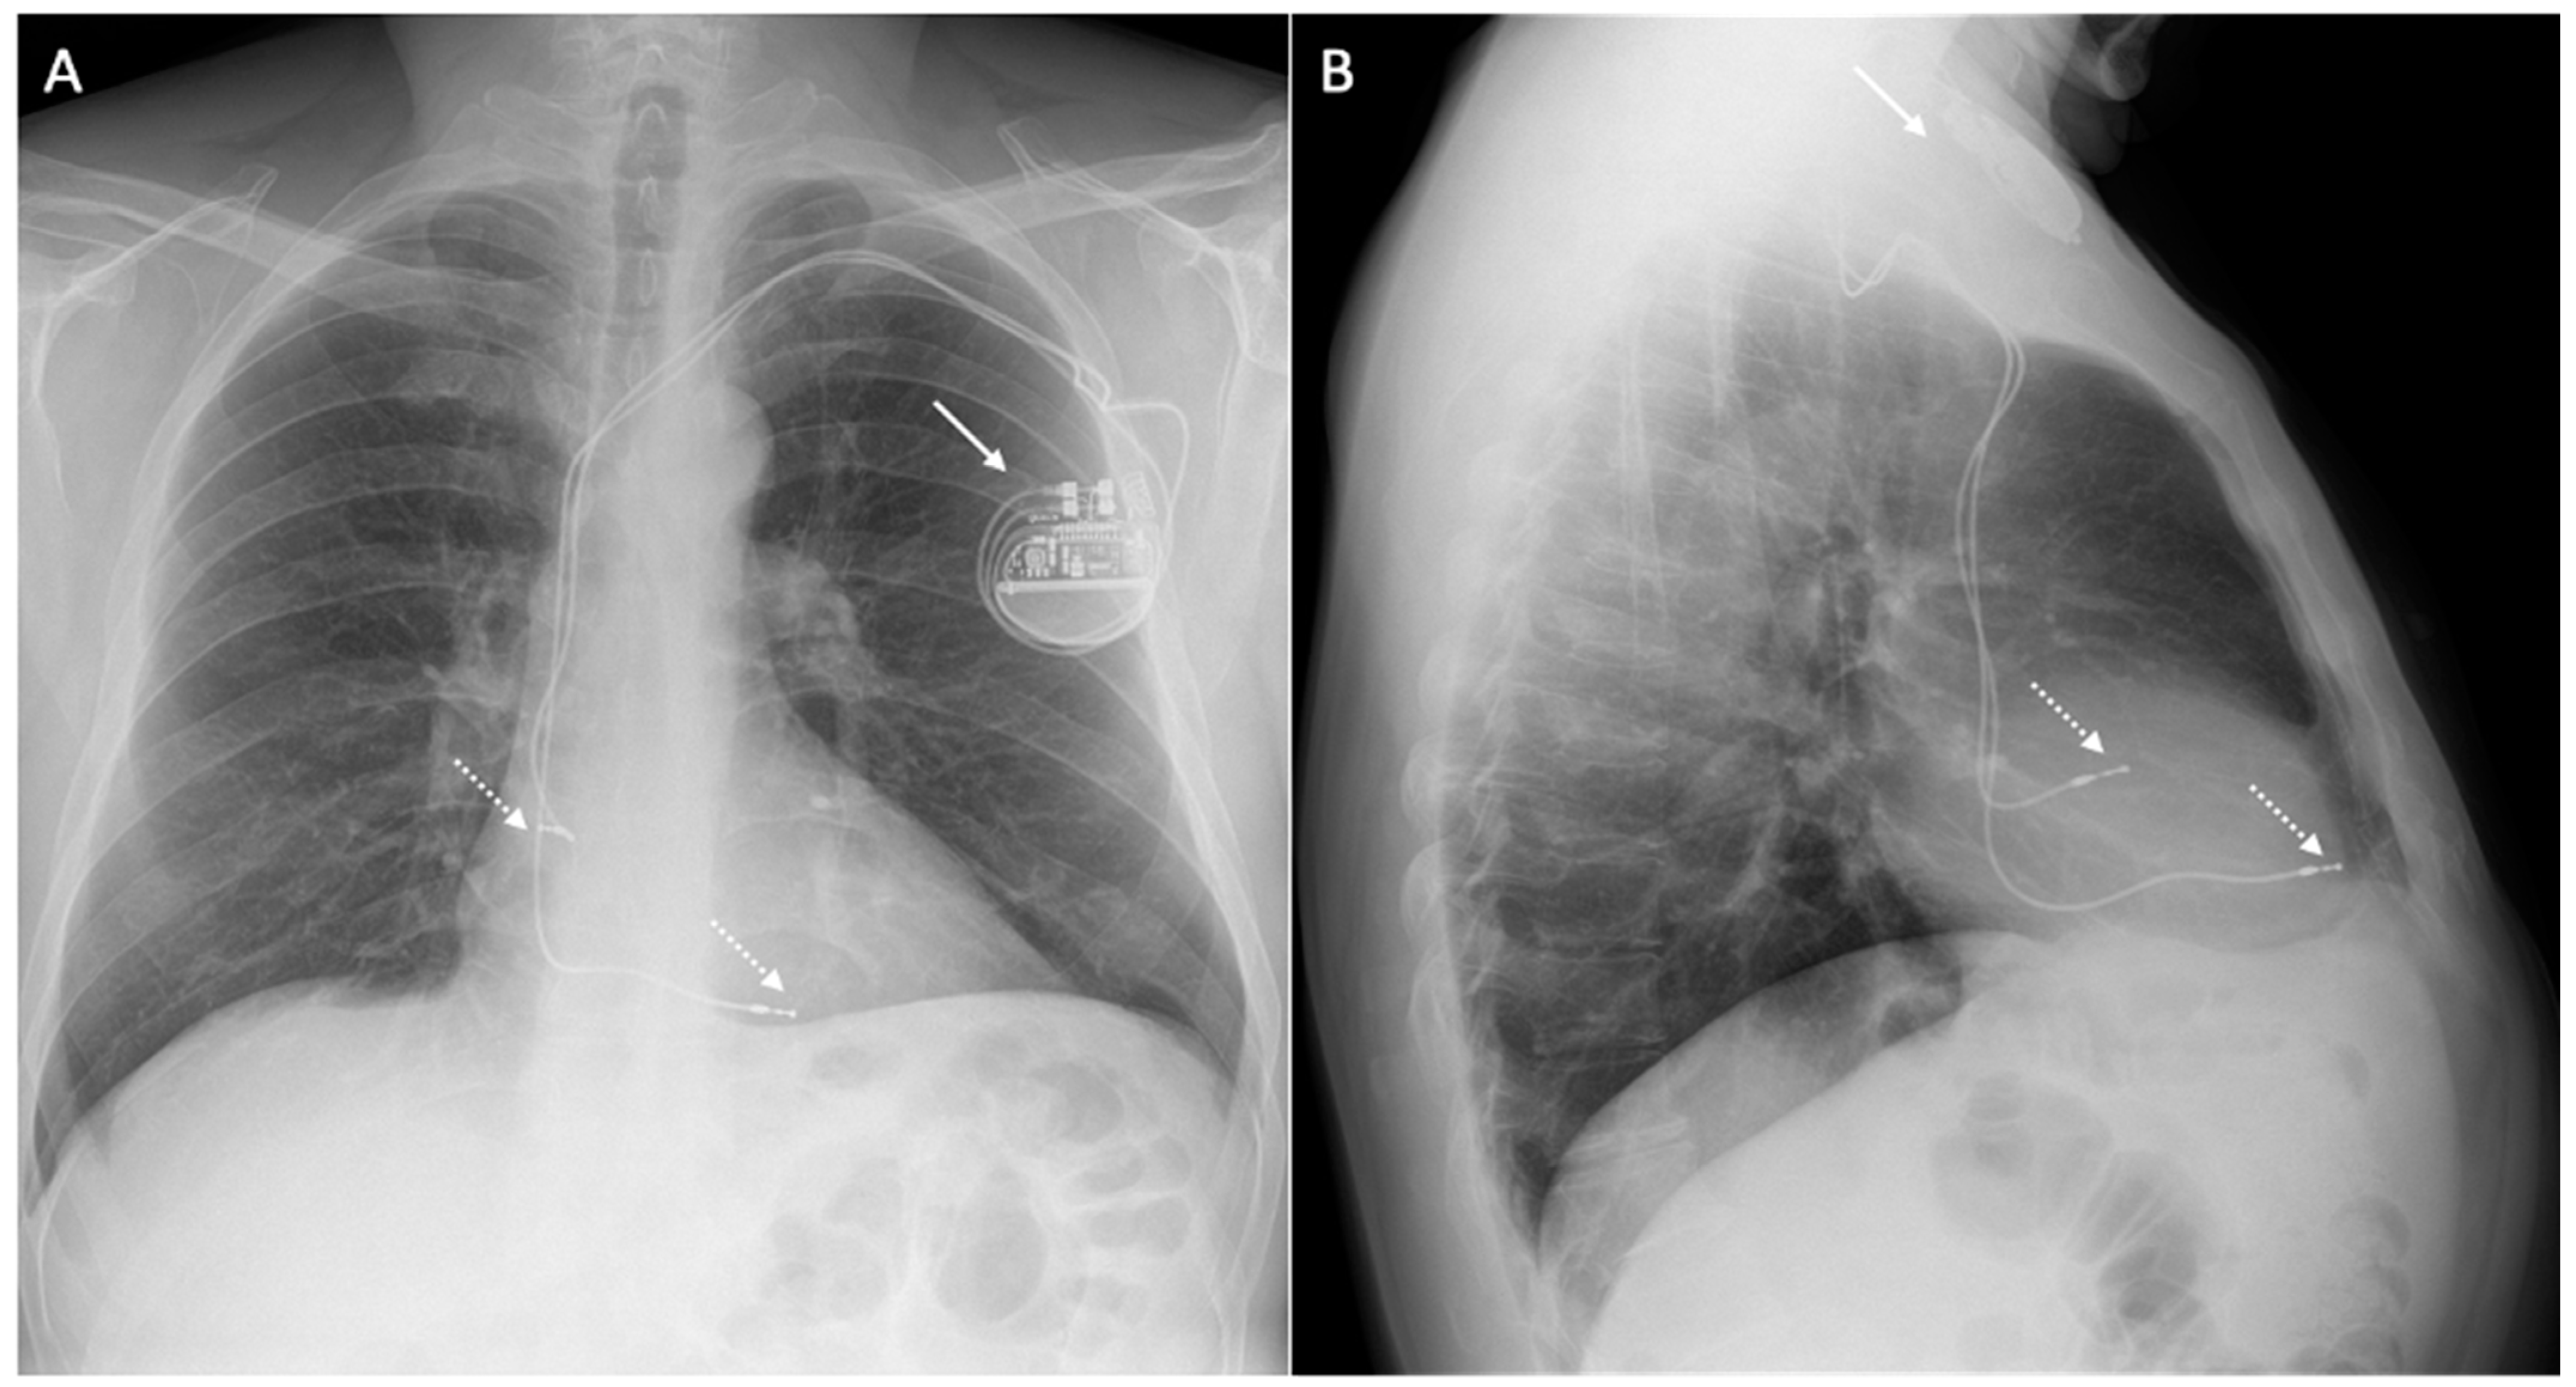

- Bučić, D.; Hrabak-Paar, M. Multimodality imaging in patients with implantable loop recorders: Tips and tricks. Hell. J. Cardiol. 2023, in press. [Google Scholar] [CrossRef]